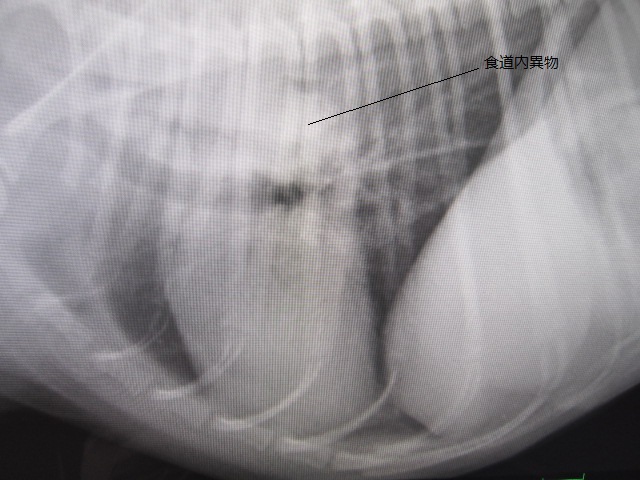

術前のレントゲンです。

食道内に異物があります。